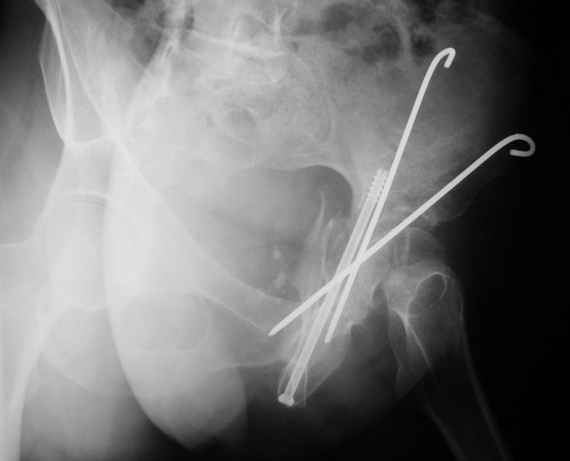

Женя! Класный перелом. Отлично репонируется изнутри таза, но лучше фиксированть сзади. Классический перелом для двустороннего доступа.

Однако есть альтернатива. Репозиция из подвздошного доступа тазовыми щипцами с разнодлинными браншами или тазовым пистолетом, а фиксация задней колонны через седалищный бугор или тазрвыми винтами 4,5 или каннюлированными 6,5 или 7,3. По-моему я посылал на ортофорум такой снимок, когда жаловался на ишемический неврит седалищного нерва через сутки после операции. Не забудь про шейку бедра - мне кажется будет хорош длинный PFN любой фирмы, какую ты найдешь, а нет так UFN + miss a nail, как это здорово делают мои земляки - Ебурбуки. Пока.

27.01.04